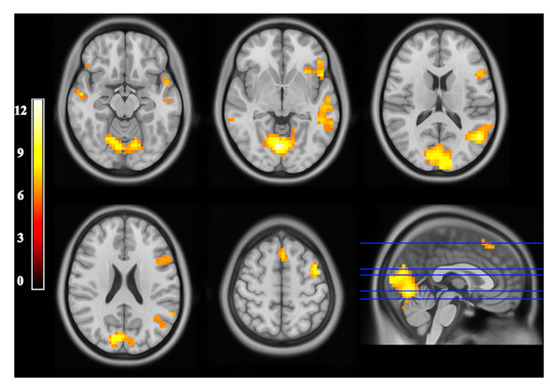

- Cassady, K.; Koppelmans, V.; Reuter-Lorenz, P.; De Dios, Y.; Gadd, N.; Wood, S.; Castenada, R.R.; Kofman, I.; Bloomberg, J.; Mulavara, A.; et al. Effects of a Spaceflight Analog Environment on Brain Connectivity and Behavior. NeuroImage 2016, 141, 18–30. [Google Scholar] [CrossRef]

- Pechenkova, E.; Nosikova, I.; Rumshiskaya, A.; Litvinova, L.; Rukavishnikov, I.; Mershina, E.; Sinitsyn, V.; Van Ombergen, A.; Jeurissen, B.; Jillings, S.; et al. Alterations of Functional Brain Connectivity After Long-Duration Spaceflight as Revealed by FMRI. Front. Physiol. 2019, 10, 761. [Google Scholar] [CrossRef]